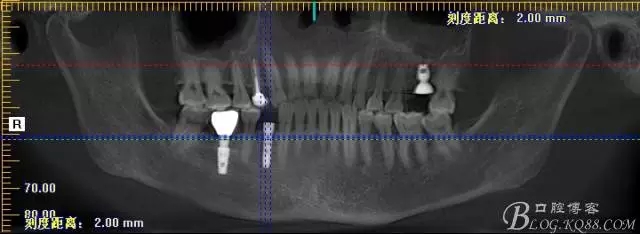

那么看下術(shù)前CBCT吧

上圖為術(shù)前CBCT情況,26號牙顯示頰根和腭根間有一比較大的區(qū)域骨頭吸收,對于即刻種植還是有難度的,植入深度需要適當(dāng)加深,那么也許使用BICON 種植體相對更加合適

上圖44號牙位做即刻種植毫無難度可言,我們要做的只是患者術(shù)后反應(yīng)更小,植入方向更好而已

術(shù)后片 能顯示間隙沒有植骨是空的

術(shù)后片顯示植入情況都可以